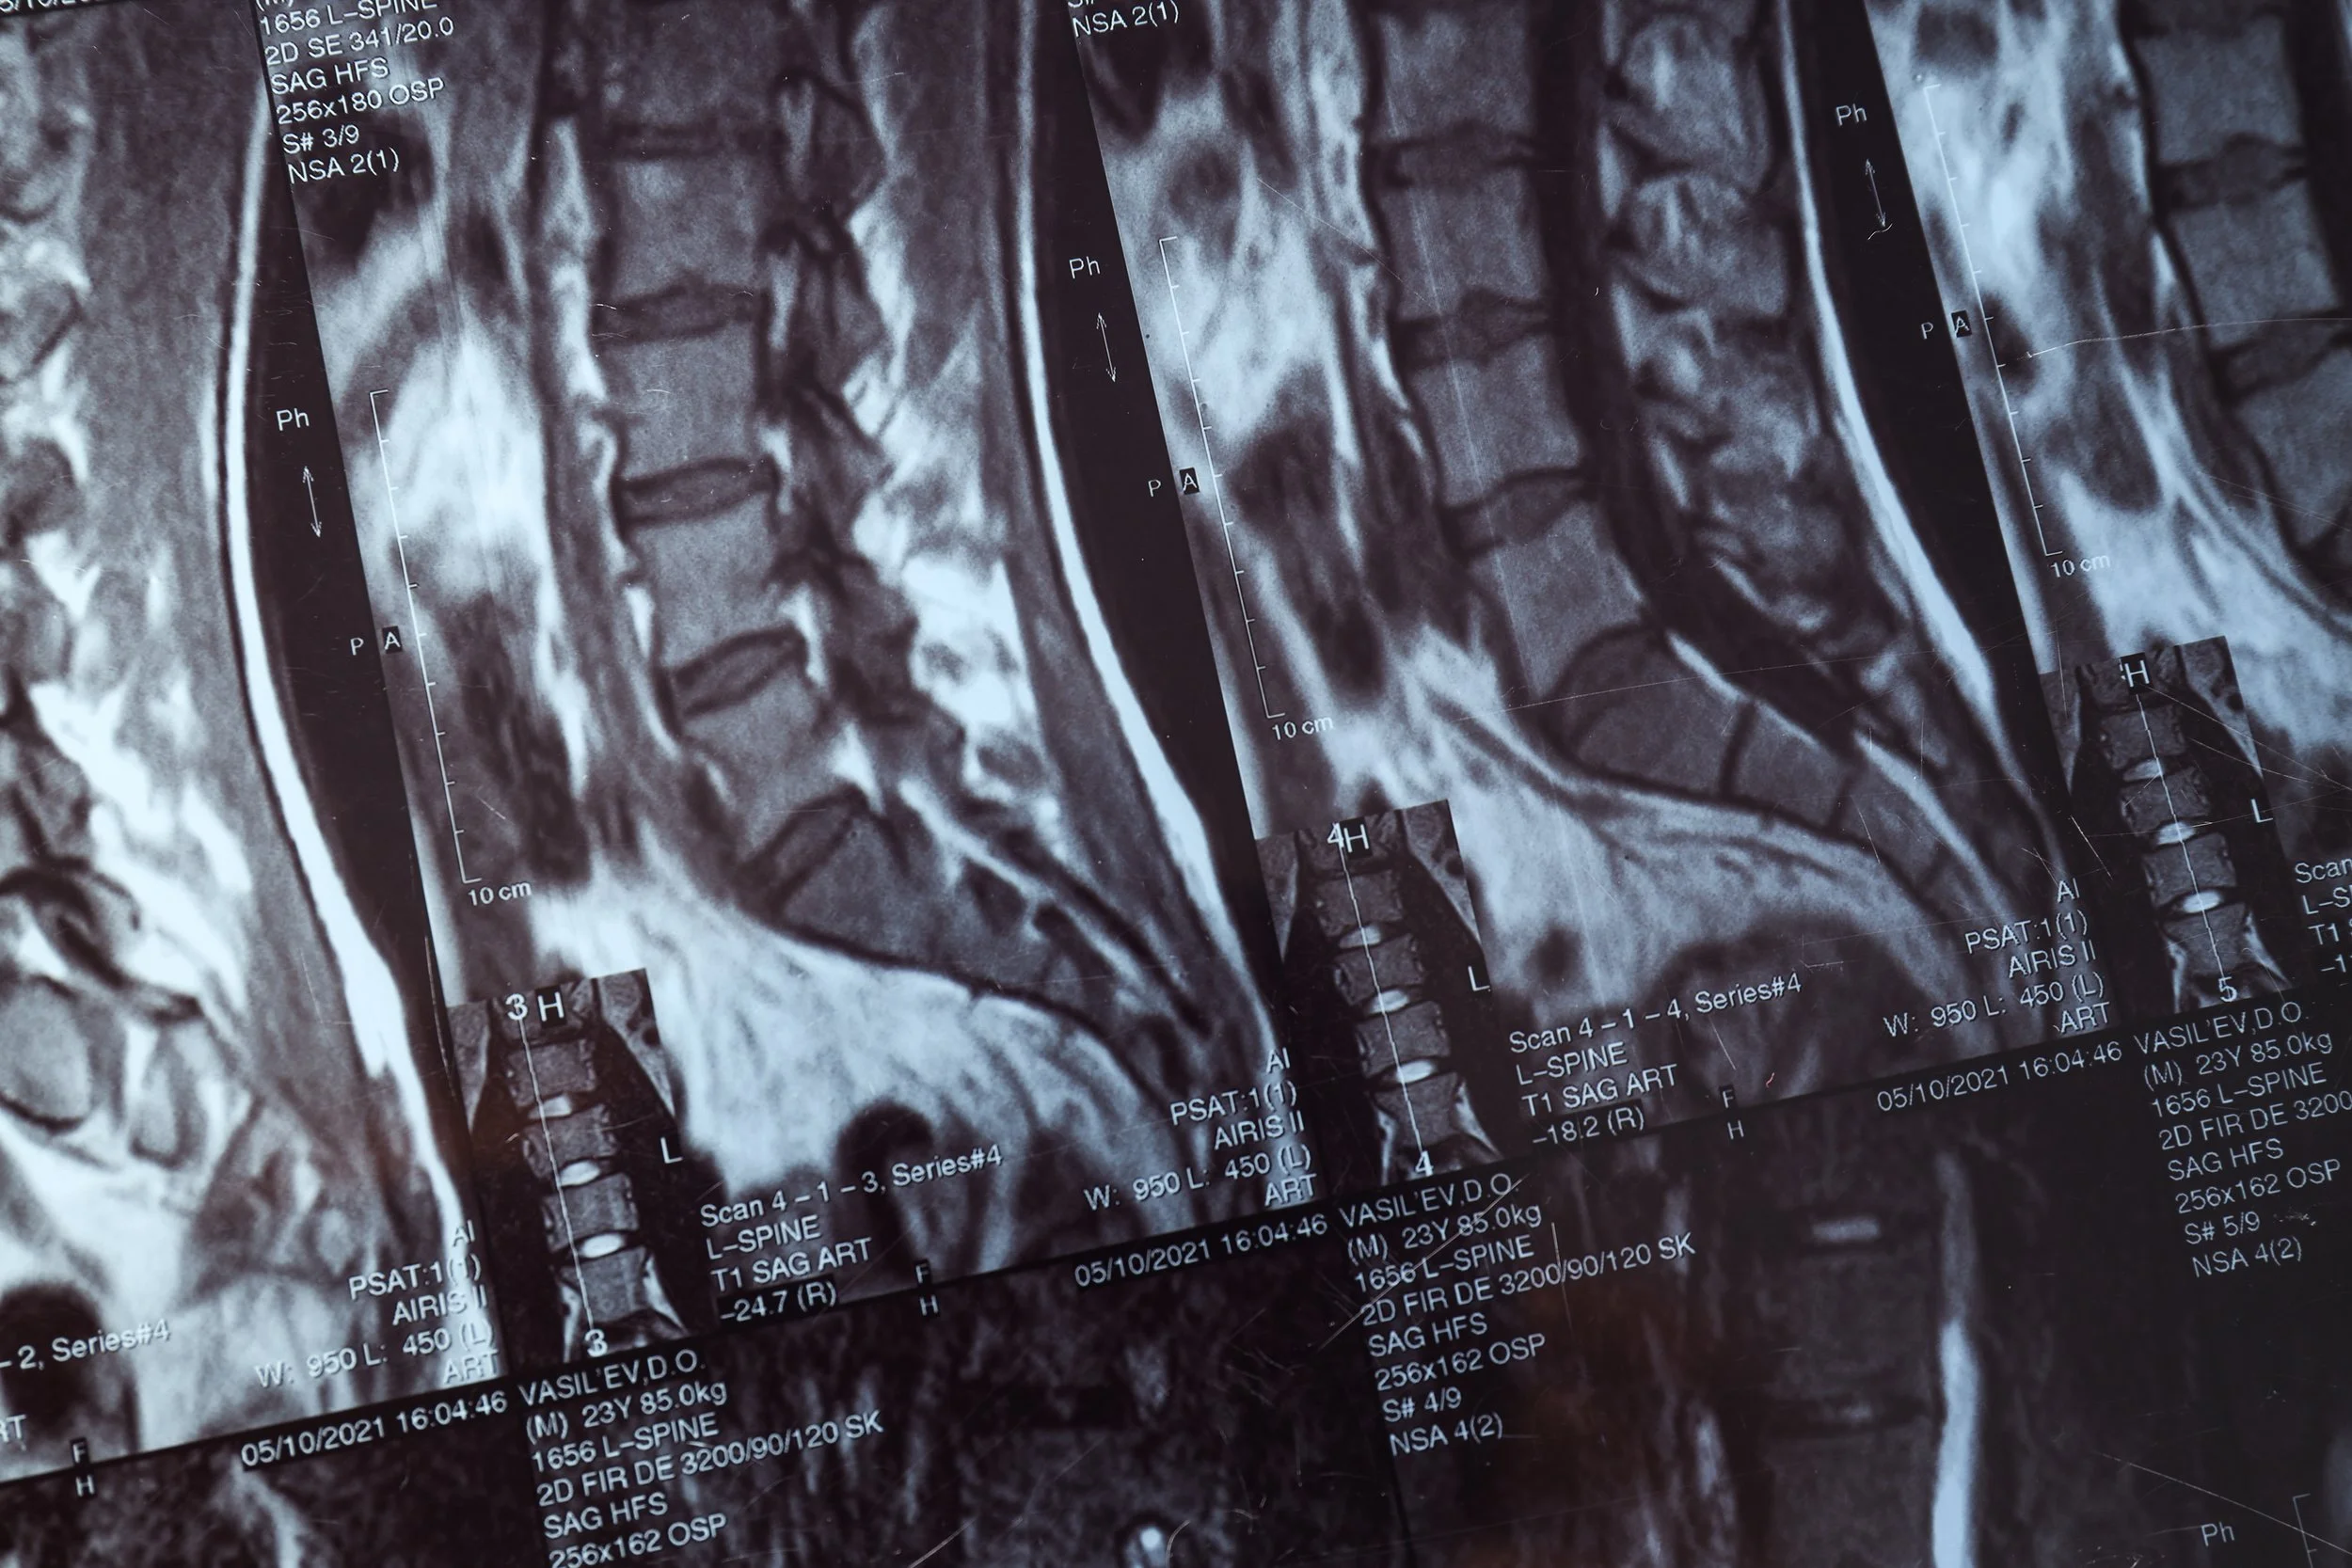

RM de cuerpo completo con difusión